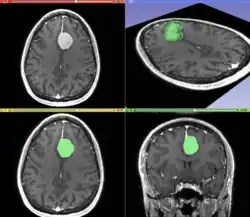

Segmentation is the process of partitioning an image into different meaningful segments. In medical imaging, these segments often correspond to different tissue classes, organs, pathologies, or other biologically relevant structures.[2] Medical image segmentation is made difficult by low contrast, noise, and other imaging ambiguities. Although there are many computer vision techniques for image segmentation, some have been adapted specifically for medical image computing. Below is a sampling of techniques within this field; the implementation relies on the expertise that clinicians can provide.

The figure "Visualization of Medical Imaging" illustrates several types of visualization: 1. the display of cross-sections as gray scale images; 2. reformatted views of gray scale images (the sagittal view in this example has a different orientation than the original direction of the image acquisition; and 3. A 3D volume rendering of the same data. The nodular lesion is clearly visible in the different presentations and has been annotated with a white line.